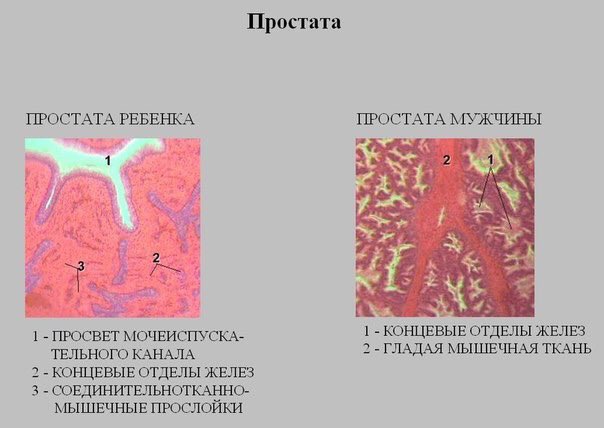

Простата детей